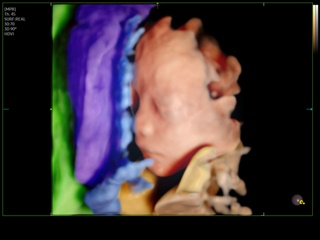

Atlas of ultrasound images - obsterics

In the section "Оbsterics" of atlas the results of ultrasonic examinations of pregnant women with different durations of gestation are represented. Here you can see images of internally organs, cerebrum, cordis and the sex of the fetus, the sonograms of multiple pregnancy, the blood flow in placenta and umbilical cord, defects of fetal`s development, etc.